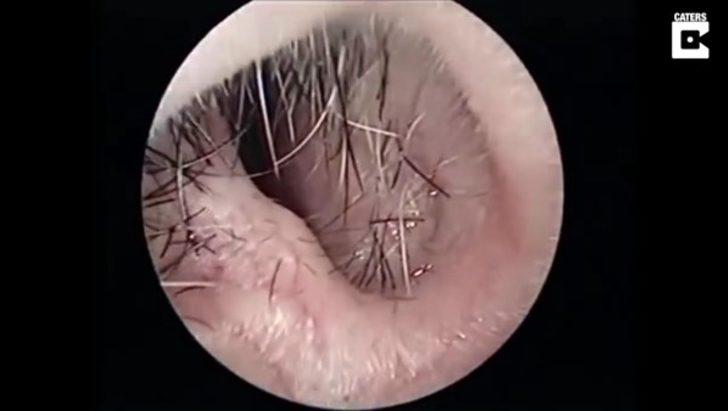

Burnunda garip bir hareketlilik hisseden hasta doktora göründü.

Doktor ise ufak bir operasyon yaptı.

Yüzerken burnuna kaçan şey doktorları bile şaşırttı